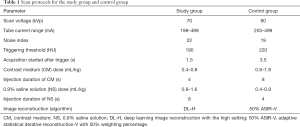

All children were scanned on a 256-row detector CT scanner (Revolution CT, GE Healthcare, USA) with prospective electrocardiography triggering. The acquisition cardiac phase windows (R-R interval) for cardiac scans were automatically selected by the scanner and were dependent on the children’s heart rates (HR) just before CCTA: 75% for HR =30–60 bpm, 40–80% for HR =60–78 bpm, 35–55% for HR =78–120 bpm, and 0–100% for HR >120 bpm. The detector z-coverage was 8–16 cm depending on the children’s heart sizes between the aorta arch and diaphragm, the matrix size was 512×512 pixels, voxel size was 0.625 mm, gantry rotation time was 0.28 second/rotation, and the display field-of-view (DFOV) for the image reconstruction was 250 mm with an image slice thickness and interval of 0.625 mm. For the study group, tube voltage was 70 kVp, and tube current was given by the automatic tube current modulation technique with an mA range of 198–499 mA to obtain a noise index (NI) of 22. NI is a parameter in the scan protocol to control radiation dose: higher NI requires a lower radiation dose. The NI value in the study group was higher than that (NI =19, see below) of the control group to reduce radiation dose, and the adjustment referenced previous research by Benz et al. (13), which indicated that the use of DLIR could reduce about 26% of image noise compared with 70% ASIR-V. Data acquisition was triggered using a bolus-tracking technique, which started at the shortest delay time (about 1.5 s based on the current modulation) after the CT value in the descending aorta became higher than the triggering threshold of 190 HU. For the control group, tube voltage was 80 kVp, NI was 19 with an mA range of 203–499 mA, and data acquisition started 3.5 s after the CT value reached 220 HU. Some children were too young to cooperate, and sedation with oral chloral hydrate (10%, 0.4 mL/kg) was applied to these children before the CT scan. The contrast medium Iohexol (350 mgI/mL, GE healthcare, Ireland) was used, and contrast dose was adjusted according to the bodyweight of the children: 0.4–0.5 mL/kg (0.5 mL/kg for 20–30 kg, 0.4 mL/kg for heavier than 30 kg) in the study group, and 0.8–1.2 mL/kg (1.2 mL/kg for 20–35 kg, 1.0 mL/kg for 35–50 kg, 0.8 mL/kg for heavier than 50 kg) in the control group. The contrast medium was injected with a fixed injection time of 4 s in the study group, followed by 0.9% saline solution with a volume double the amount of contrast medium and injected in 8 s. For the control group, the contrast medium was injected with a fixed injection time of 8 s, followed by 0.9% saline solution with a volume half the amount of contrast medium and injected in 4 s. All injections were performed using a double head injector (EmpowerCTA+, Bracco Injeneering S.A., NJ, USA). Scan protocols for the study group and control group are listed in Table 1.

Full table